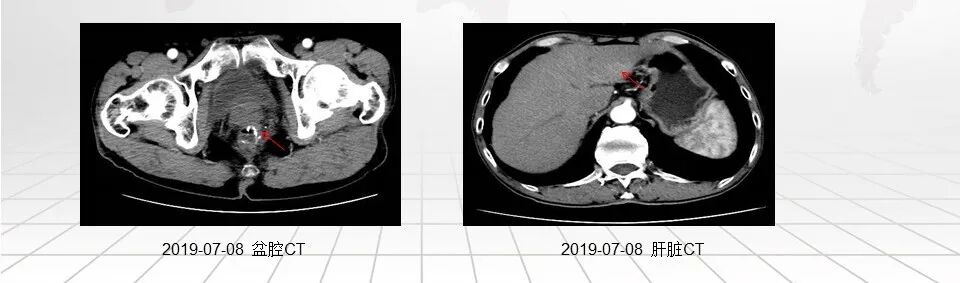

2019-07-08 患者复查腹部CT检查提示:盆腔术后改变,请结合临床;肝S3段稍低密度,考虑转移瘤。诊断:直肠癌术后肝转移(IV期)

经医院MDT会诊后,考虑患者肝脏转移病灶局限在肝S3段,可切除。建议患者行肝S3段转移病灶的切除。

患者于2019年7月17日在我院肝胆外科于全麻下行左外叶肝切除+胆囊切除,手术顺利,术后予以抗炎补液、护胃制酸、保肝退黄、维持水电解质平衡、清洁换药等对症处理。

术后病理提示:送检部分肝组织一件,大小11cm×7.5cm×4cm,距肝切缘1cm见一大小4cm×3cm×2cm肿块;镜检为中分化腺癌伴坏死,组织学形态结合临床病史,考虑肠腺癌转移可能性较大。切缘未见癌;周围肝组织肝细胞轻度水肿、淤胆。慢性胆囊炎。